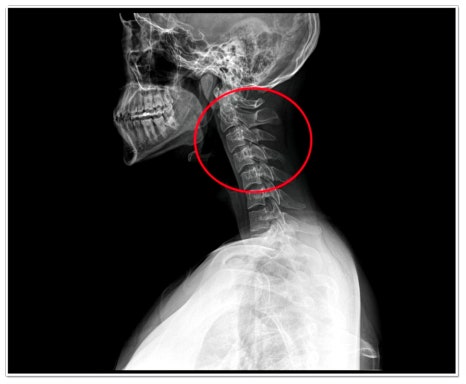

거북목, 일자목, 라운드 숄더는 현대인에게 매우 흔한 체형 문제입니다.

이 세 가지는 사실 서로 긴밀하게 연결되어 있죠.

지금 한번, 목을 앞으로 쭉 내밀어보세요.

어깨가 자연스럽게 말리고 등이 굽어지지 않나요?

이때 어깨 관절과 견갑골의 위치가 어긋나면서 상체의 균형이 무너지게 됩니다.

평소 컴퓨터나 스마트폰을 오래 보는 습관이 있다면, 자신도 모르게 목이 앞으로 쏠리고 어깨가 움츠러드는 거예요.

이렇게 굳어진 자세는 근육 불균형을 유발해, 교정이 점점 어려워집니다.

단순한 스트레칭만으로는 근본적인 개선이 어려운 이유가 바로 여기에 있습니다.